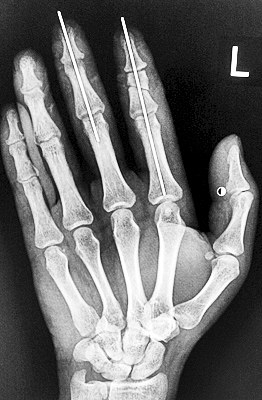

術(shù)后X光顯示,骨骼對位良好。

最終,盧微波和團隊找好了需要的血管和神經(jīng),做好標(biāo)記后,開始固定食指骨骼、吻合肌腱,最后在顯微鏡下用直徑20微米的無創(chuàng)顯微縫合線開始吻合血管和神經(jīng)。

在經(jīng)過兩個多小時手術(shù)后,早上8時許,盧微波下令松止血帶,數(shù)十秒后男子蒼白的食指逐漸紅潤起來,食指在離體10個小時后恢復(fù)血運。

緊接著,盧微波又開始中指再植手術(shù)。上午10時許,中指在離體12小時后也成功恢復(fù)血運。